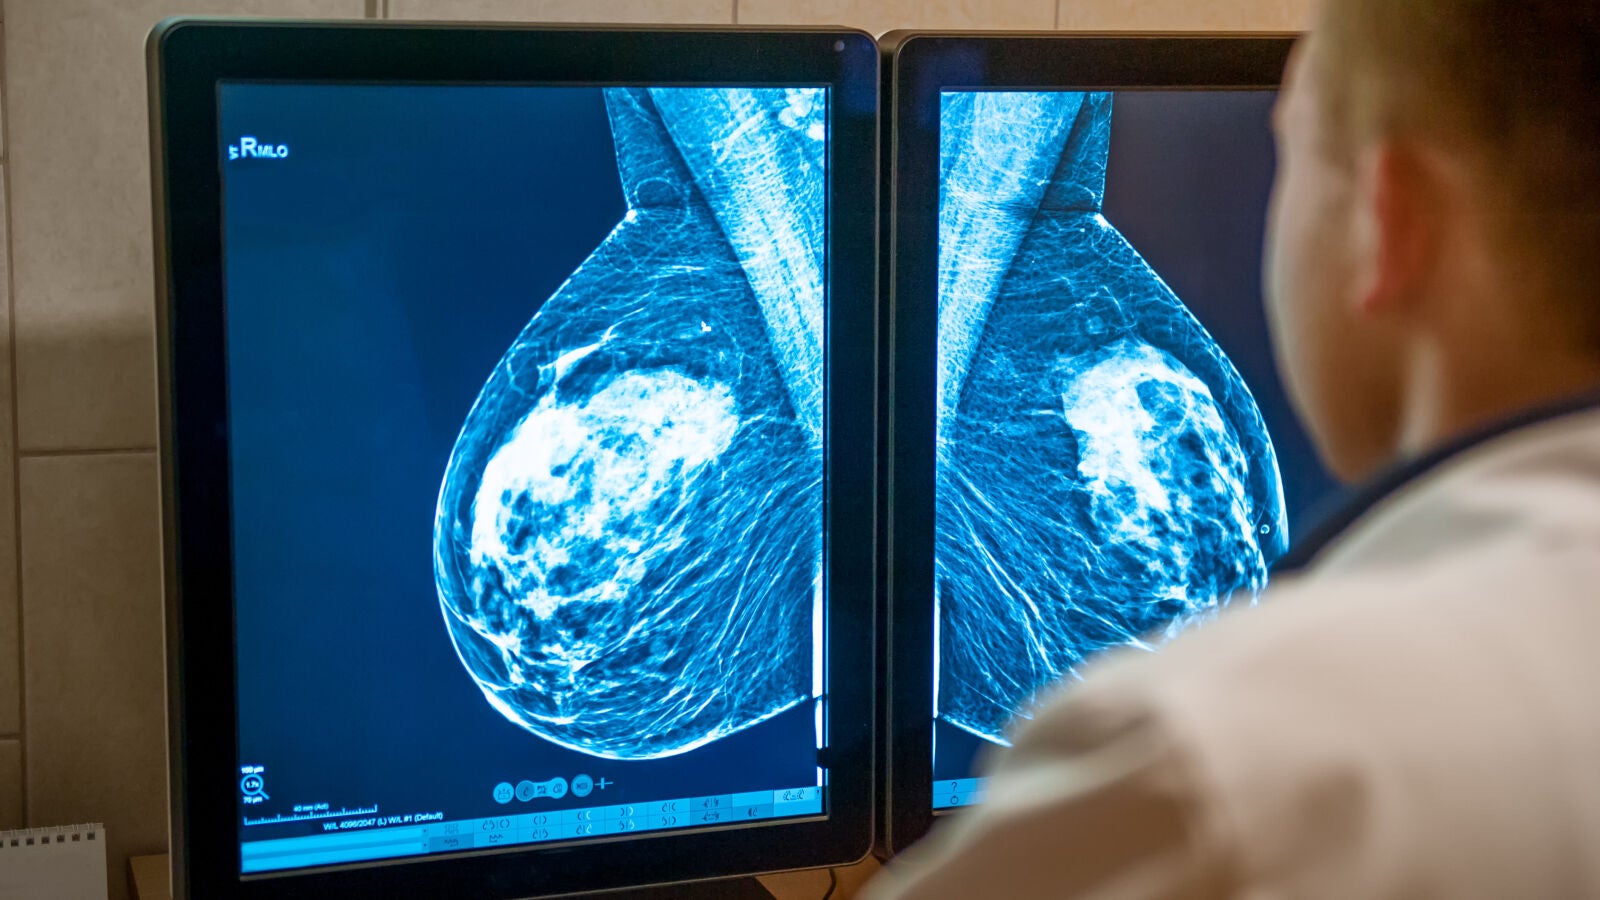

Cada hora, 4,3 mujeres serán diagnosticadas este año de cáncer de mama en España. No todas necesitarán quimioterapia para reducir el riesgo de que el cáncer reaparezca. De hecho, aunque la quimioterapia sigue siendo un tratamiento eficaz y necesario para algunos casos, las pautas de tratamiento han cambiado y van a seguir cambiando, de modo que no se recomienda hoy a tantas personas como hace 20 años y en el futuro se indicará a muchas menos.